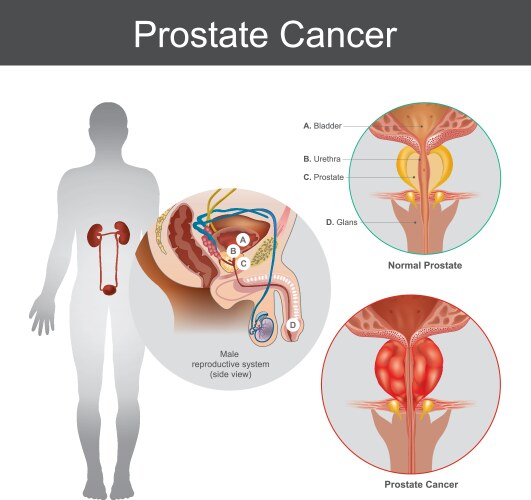

- Bph

- Prostate

- Treatment

- Enlarged

- System

- Anatomy

- Bladder

- Cancer

- Disease

- Oncology

- Tumor

- Prostatic

- Reproductive

- Urology

- Carcinoma

- Urethra